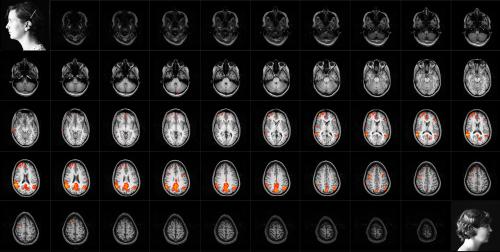

#LLL# Marta De Menezes, Functional

portraits (Self-portrait while drawing),

2003, installazione:

video proiezione su tela, cm 200x200

Ancora identità in cerca di definizione nei ritratti Functional Portrait di De Menezes e Somato-Landscape di Neira. Entrambi realizzati sottoponendosi a risonanza magnetica, il primo mostra la risposta emodinamica correlata all'attività neuronale in una precisa azione (l’artista che disegna), mentre il secondo è un ritratto “all’osso”, essenziale e organico, eppure ancora capace di raccontare le emozioni e l’intimità del soggetto.